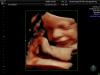

Доброй ночи 🖤 девочки кто делал 3д узи и на каких сроках )? И девочки , есть ли тут кто из Сочи ?

@julia_l_sochi, ну полностью не помещается уже на картинку . А кусочками .

Вообще рекомендуется до 30 недель, чтобы хорошо было видно) потом не будет помещаться на монитор. Я не делала) на обычном узи хорошо видно было личико) я из Сочи

В 34 недели сделала так все хорошо было видно) Я из Адлера))

Я делала в 22,и Гаяна сказала если хочу 3д то приходить в 31-32 недели на УЗИ,там и посмотрят и уже фото хорошие сделать можно. А то позже не влезет в кадр 😃

30 недель, в Армеде, 2500 руб. Врач Журавлев 👍🏻